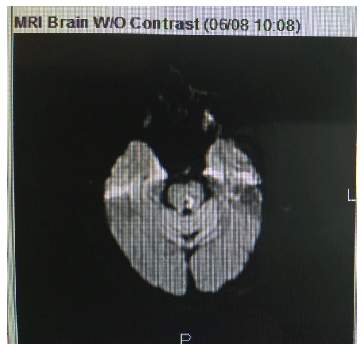

磁共振成像(MRI)/磁共振血管造影(MRA)显示左侧脑桥梗死累及外展神经运动核区域。这一结果导致误诊(图4)。

图4:0.9 × 0.4 cm累及左正中旁、中央和后脑桥/被盖的受限扩散区,与急性梗死累及外展神经运动核区域一致(箭头指向病变)。